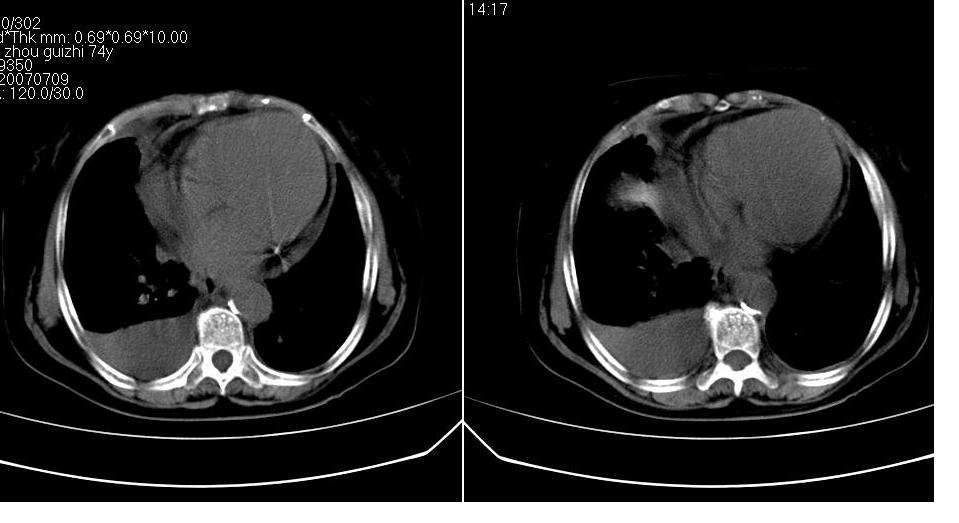

以下是引用liaizhi在2007-7-11 15:41:00的发言:[br]两肺纹理增粗,肺门影增大,气管支气管通畅。升主动脉壁及冠状动脉壁钙化。左房左室稍扩大。心包积液,胸腔积液。考虑冠心病并心功能不全,肺水肿,胸腔积液。

以下是引用zhangzhongshou在2007-7-11 13:16:00的发言:[br]1、冠状动脉钙化[br]2、心包积液[br]3、右侧胸腔积液[br]大家都考虑心衰,冠状动脉钙化、肺纹理增强,胸腔积液、心包积液,表面上是支持,但是为什么右侧有较多积液,左侧没有呢? 如果用结核性胸膜炎,并结核性心包炎也可解释,请楼主进一步提供临床资料。

以下是引用zrs在2007-7-11 14:40:00的发言:[br]支持心衰,心衰所至的胸腔积液常常是右侧多